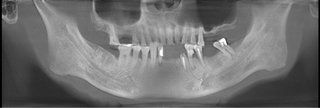

牙齿情况:口内牙齿松动,牙齿根尖有炎症,多颗牙齿缺失

经过检查,郑苍尚院长发现谢铭勋口内上颌缺牙3颗,下颌缺牙6颗,余牙松动,牙根尖伴有炎症,且因长期牙周疾病,牙槽骨有中度萎缩,最好的治疗方案就是选择种植牙。根据谢铭勋口内的情况,郑苍尚院长为他量身定制了麦芽口腔微创微痛种植牙技术。

口腔全景片